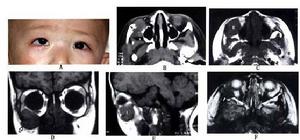

雖然眼眶侵犯較少,但可侵及骨質,產生嚴重的骨破壞。眼部症狀包括眼球突出、眶周可觸及腫塊等眼眶占位病變症狀和體徵。病變也可累及顱內顯示多發灶由於病灶較小,多無顱內症狀。

影像學檢查:超聲、CT和MRI很類似朗格漢斯細胞組織細胞增生症,表現為眼眶軟組織塊影,眶骨及顱內多發性骨破壞。MRI顯示眶顱多發病灶如骨破壞明顯,X線可顯示顱內多發性骨破壞病灶,邊界清楚,但不整齊。